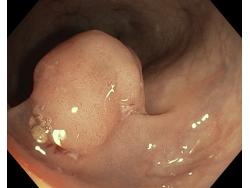

Polipy